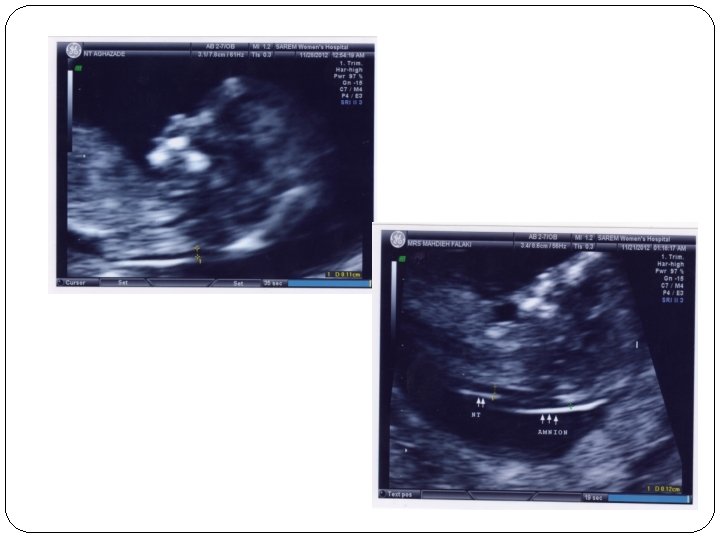

NT measurement - CRL: 45 -84 mm (11 w-13 w 6 d) - TAS(95% success)=TVS(other 5%) - Waiting for spontaneous fetal movement, asking the mother to cough, tapping the maternal abdomen(amnion membrane!)

NT measurement - Good work after 80 -100 sonography and at least 10 min - Study on 100, 000 cases: normal: 1. 2 (11 w) to 1. 9(13 w 6 d) abnormal: above the 95 th centile(>=3 mm)